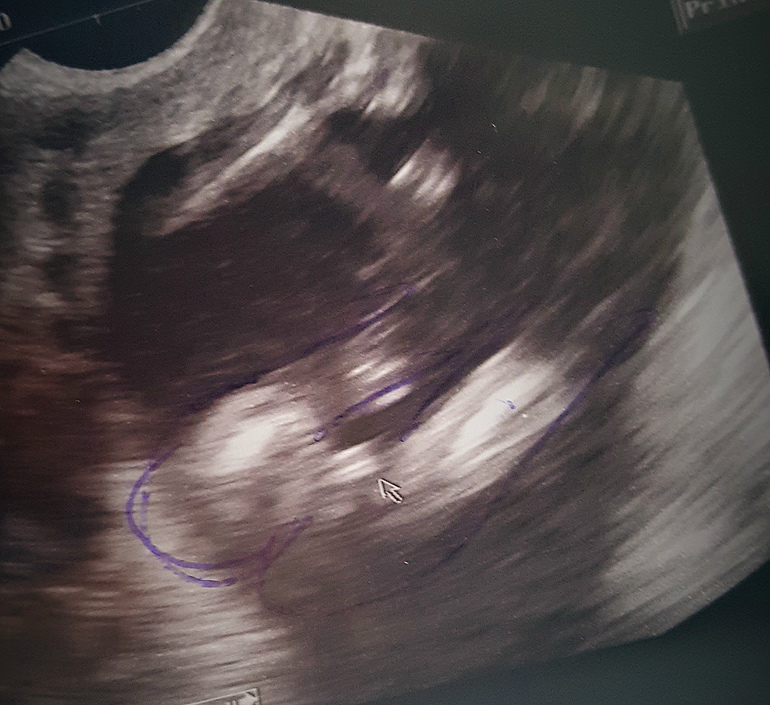

Девочки, помогите разобраться))) в 12 недель говорили мальчик, в 14 не видно ( часто хожу на УЗИ наблюдали плаценту, низкое крепление), в 16 говорят девочка и фотку сделали даже) доча есть -10 лет) муж мечтал о мальчике🤦🏻♀️И мне прям неприятно что так явно, но я то очень жду свою вторую принцессу) явно девчудя раз между ножек нет ничего)))

фото такое не совсем четкое

у меня в 16 нед с мальчиком такое было, я тоже как то не уверена была, думала что ошибка возможна